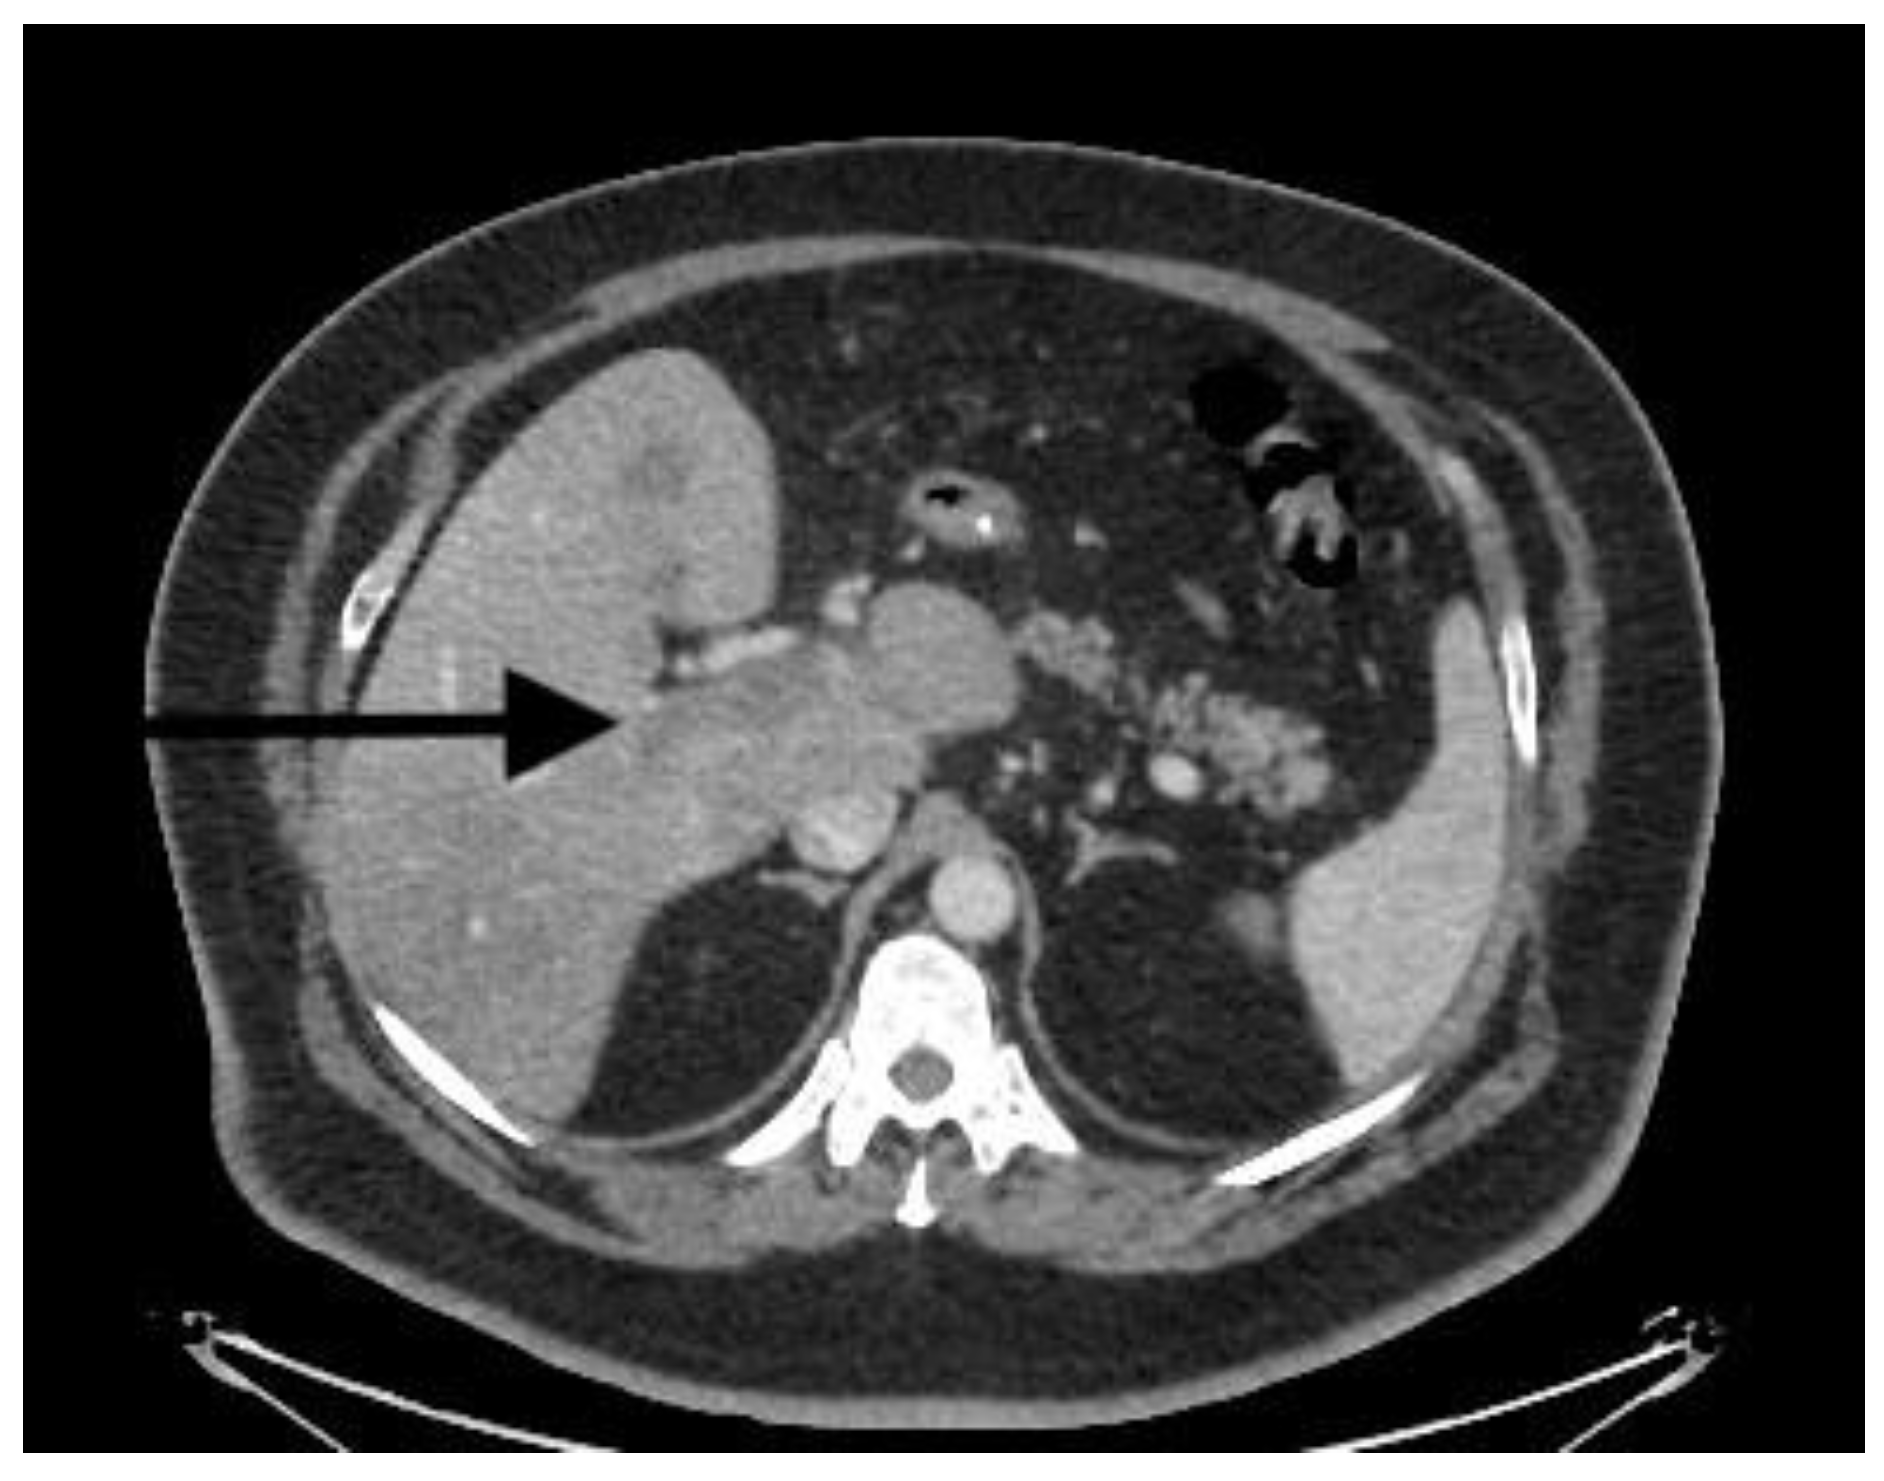

| CT scan | Nonocclusive PVT, posterior right branch, and partial superior mesenteric vein | Nonocclusive PVT, right branch, and partial superior mesenteric vein | Extensive occlusive, portal, splenic, and mesenteric thrombosis; ascites evidence of small-bowel hypoperfusion | Partial PVT |